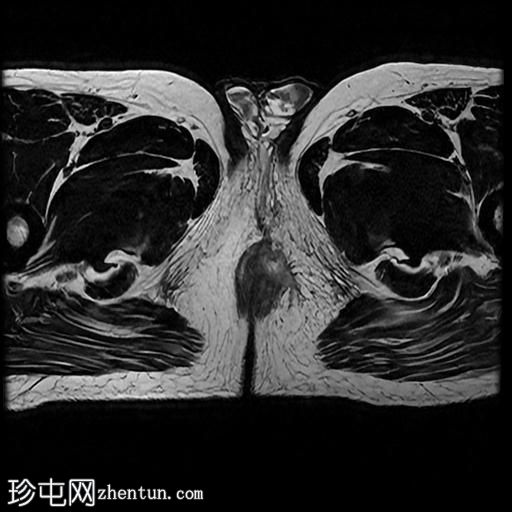

MRI

轴向位

T2

轴向位T2

一条68毫米厚的强化通道始于左侧肛周区域,向上穿过肛门内外括约肌,在2点钟方向开口于肛管。

无脓肿形成。

MRI成像特征与所述左侧经括约肌肛周瘘相符。